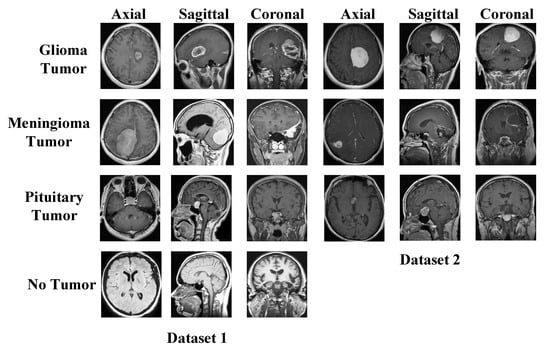

We have used two datasets in this research to show the general classification ability of the proposed model. The used both datasets are publicly available, and these are brain tumor datasets. These datasets were downloaded from Figshare and Kaggle platforms. There are three classes in the Figshare dataset, and the Kaggle dataset has four classes. Therefore, we used Kaggle Dataset for training. Sample images of these datasets are demonstrated in Figure 1.

Figure 1.

Sample images used in the two datasets. Dataset I: Kaggle dataset and this dataset have been used for training, Dataset II: Figshare dataset.

2.1. Dataset I

The dataset consists of four classes of axial, sagittal, and coronal section images. The data is divided into training and test data. The glioma tumor class contains 100 images in the test folder and 826 images in the training folder. The meningioma tumor class contains 115 images in the test folder and 822 images in the training folder. There are 105 images in the test folder and 395 images in the training folder for the no-tumor class. The pituitary tumor class contains 74 images in the test folder and 827 images in the training folder. In this study, the images in the training and test folders were combined. In total, there are 926 images in the glioma tumor class, 937 in the meningioma tumor class, 500 in the no-tumor class, and 901 in the pituitary tumor class. The sum of the number of images in all classes is 3264 [37].

2.2. Dataset II

The dataset consists of three classes of axial, sagittal, and coronal section images. In the meningioma class, 82 patients had 708 MR images. Of the meningioma tumor class images, 209 are axial, 268 are coronal, and 231 are sagittal. There are 1426 MR images of 89 patients in the glioma tumor class. Of the glioma tumor class images, 494 are axial, 437 are coronal, and 495 are sagittal. There are 930 MR images of 62 patients in the pituitary tumor class. Of the pituitary tumor class images, 291 are axial, 319 are coronal, and 320 are sagittal. The dataset consists of 3064 T1-weighted contrast-enhanced MR images of 233 patients [38].